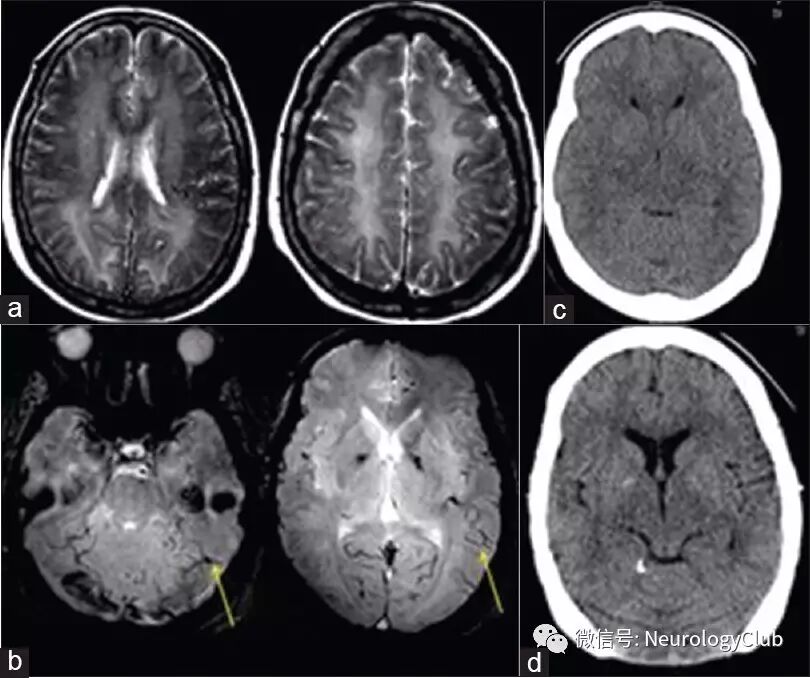

头颅MRI提示弥漫对称的白质病变,脑沟/小脑裂可见一突出静脉,Galen静脉/直窦区血管影明显。未见动脉性或静脉性梗死。

(图:a:T2WI可见双侧大脑半球对称融合的高信号病灶;b:梯度回波序列可见双侧小脑裂和大脑沟突出的静脉[低信号,线状],未见明显脑实质血肿或静脉窦血栓形成;c:头颅CT提示弥漫脑水肿,脑沟模糊,额角受压;d:治疗后复查CT可见额角恢复正常,外侧裂可见,脑沟较前清晰)

血管造影证实为硬脑膜动静脉瘘(DAVF)(直窦[靠近Galen静脉],窦汇处)。可见明显的逆行静脉窦引流至上矢状窦,右横窦,皮层浅静脉和深静脉系统。

患者行动静脉瘘栓塞治疗。术后患者认知功能改善(MMSE评分14/27)。嗜睡和肌阵挛完全消失。